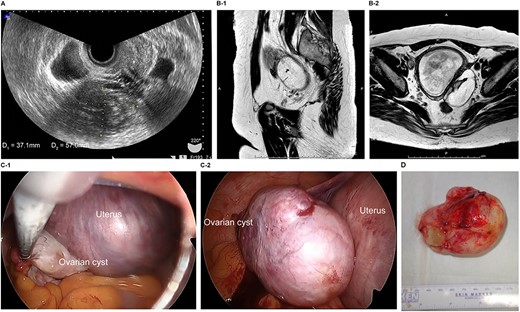

The patient was a 40-year-old, gravida 1, para 0 woman with no familial or medical history. She conceived naturally and was diagnosed with a left ovarian cyst at 5 weeks gestation by another doctor. She was referred to our hospital for further examination and operation. TVUS revealed a fetus in the uterus and a mass 6 cm in diameter on the left ovary, which appeared to be a dermoid cyst. MRI revealed left ovarian cystic tumors with fat tissue. The laboratory values, including the levels of tumor markers (e.g. CEA, CA-125, CA 19–9 and SCC) were within the normal limits. We performed single-port laparoscopic surgery at 17 weeks and 0 days gestation to remove the left ovarian cysts. The procedure was performed within 59 minutes, and there were no complications (Fig. 2).

Imaging studies and laparoscopic views and specimen photograph of case 2. (A) Transvaginal ultrasound image showing an ovarian cyst. (B-1) Sagittal T2-weighted magnetic resonance image (MRI) showing an ovarian cyst. (B-2) Axial T2-weighted MRI showing an ovarian cyst. (C-1) Gestational uterus: ovarian cyst was moved from the pouch of Douglas. (C-2) Ovarian cyst was moved and located on the gestational uterus. (D) Ovarian Cyst.